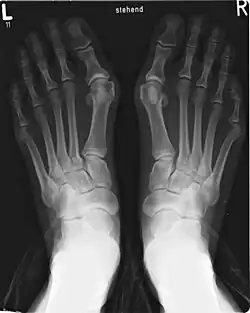

Die Tarsometatarsalgelenke (Articulationes tarsometatarsales, „Fußwurzel-Mittelfuß-Gelenke“, abgekürzt: „TMT I-V“) sind die Gelenke zwischen den Keilbeinen und dem Würfelbein und den Basen der Mittelfußknochen. Es handelt sich um straffe Gelenke (Amphiarthrosen), das heißt, sie lassen nur geringfügige Bewegungen zu. Bei stärkeren Belastungen sind sie an den Kippbewegungen des Fußes (Pronation und Supination) beteiligt. Beim Menschen werden drei Tarsometarsalgelenke unterschieden, deren Gelenkspalte die Lisfranc-Gelenklinie bilden.

Das innenseitige (mediale) Tarsometatarsalgelenk wird vom inneren Keilbein (Os cuneiforme mediale) und dem ersten Mittelfußknochen gebildet. Im mittleren Tarsometatarsalgelenk stehen das mittlere und äußere Keilbein (Os cuneiforme intermedium und laterale) mit den Basen des zweiten und dritten Mittelfußknochen in Verbindung. Das äußere (laterale) Tarsometatarsalgelenk wird vom Würfelbein und dem vierten und fünften Mittelfußknochen gebildet.

Bei einer Hallux-valgus-Fehlstellung kommt es im ersten Tarsometatarsalgelenk zu einer medialen Abduktion zum Fußinnenrand und einer Varus-Fehlstellung des ersten Mittelfußknochens (Metatarsus primus varus). Entsprechend setzen einige Operationsverfahren zur Korrektur des Hallux valgus an diesem ersten Tarsometatarsalgelenk an, besonders die Lapidus-Arthrodese als korrigierende Versteifung des Gelenks.